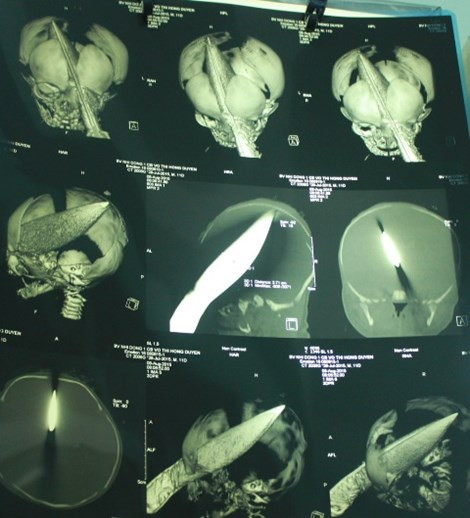

| Bệnh nhi nhập viện trong tình trạng con dao còn nguyên trong đầu. |

| Các BS đã lấy con dao ra khỏi đầu bệnh nhi. |